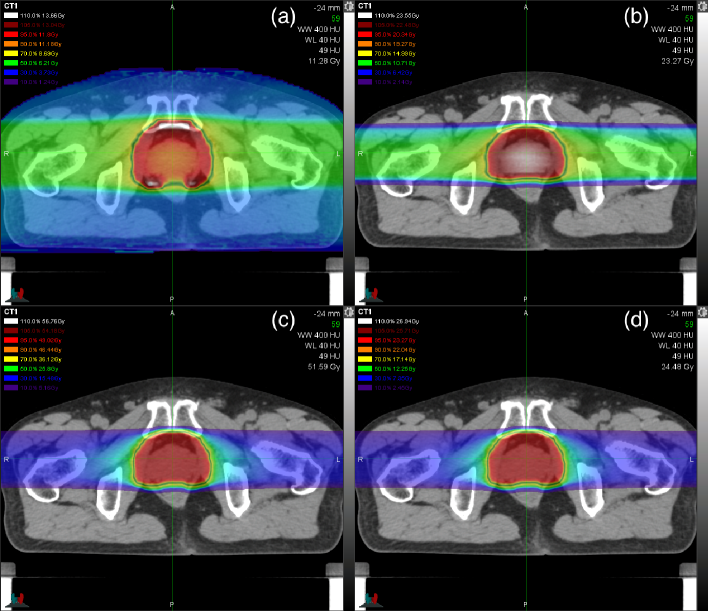

Figure 4: Planning CT image of the prostate-cancer patient in the isocenter plane with green crosshairs for the right–left and anterior–posterior axes and overlaid color wash (10%, 30%, 50%, 70%, 90%, 95%, 105% and 110%): (a) dose-mean α/β𝛼𝛽\alpha/\beta ratio relative to 12.42 Gy, (b) total physical dose relative to 21.41 Gy, (c) total RWD relative to 51.6 Gy (RBE) and (d) ERD relative to 24.49 Gy.

Figure 4 shows the dose distributions calculated for the actual prostate-cancer treatment. The dose-mean α/β𝛼𝛽\alpha/\beta-ratio and physical-dose distributions were gentle in the opposing beam arrangement while the α/β𝛼𝛽\alpha/\beta ratio was high in the anterior and posterior sides of the prostate and the physical dose was high in the central prostate. The relative difference between the clinical dose in figure 5(c) and the ERD in figure 5(d) was minor due to small quadratic-term contribution at the level of 4.3 Gy (C) or 1.78 Gy (RBE) as consistent with figure 3.